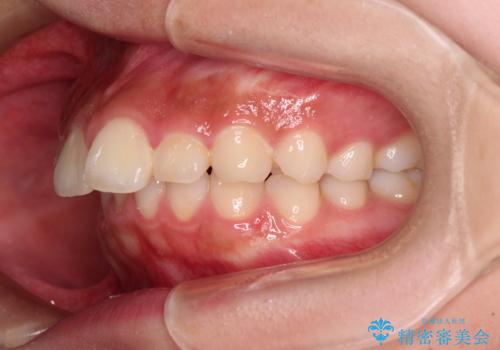

- 飛び出した上顎前歯と、閉じにくい唇、口元の突出した印象の横顔を気にして来院された患者様です。

骨格的な上顎前突であり、上下前歯の前後的な距離が大きいため、上顎は左右第一小臼歯を、下顎は左右第二小臼歯をそれぞれ2本抜歯することで前歯が接触するようにし、さらには奥歯の咬み合わせも、より理想的な状態へ近づけていくこととしました。

3年以上はかかる難症例であるため、表側のワイヤー装置にて治療を行うこととしました。

事前の予想通り、長期間を要する治療となりましたが、横顔の印象が劇的に変化し、患者様には大変満足していただきました。